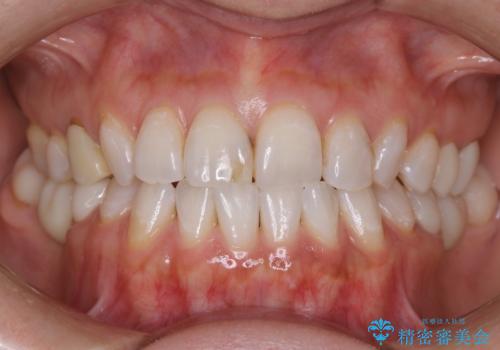

[ 前歯のセラミック治療 ] 短期間で歯並びを治したい

![[ 前歯のセラミック治療 ] 短期間で歯並びを治したいの症例 治療前](https://seimitsushinbi.jp/wp/wp-content/uploads/2022/07/68f8dbc76371dd3ce89027a3fa5c08e4-500x350.jpg?v=1657077061)

![[ 前歯のセラミック治療 ] 短期間で歯並びを治したいの症例 治療後](https://seimitsushinbi.jp/wp/wp-content/uploads/2022/07/651788be749c2e6e13f4a14213242ca5-500x350.jpg?v=1657077103)